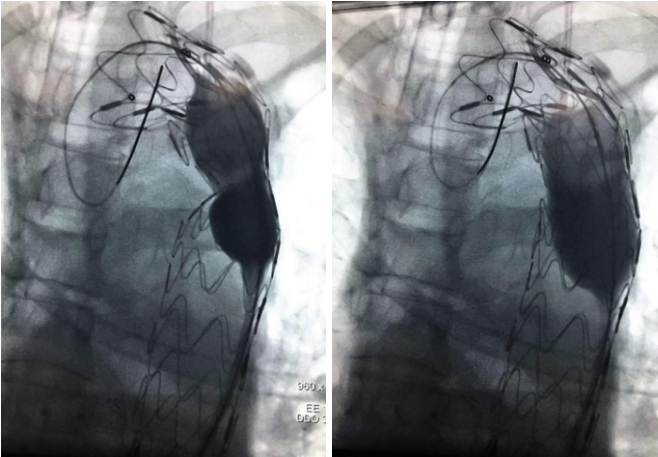

由于患者的主动脉根部扭曲程度很大,猪尾导管无法置于无冠窦底,钟炜教授在释放时通过精准控制输送系统和适时造影,最终完美完成了瓣膜的释放。

主动脉根部扭曲程度大

猪尾很难到达主动脉根部,释放难度大

植入VitaFlow TAV 27的瓣膜,进行定位释放

瓣膜释放完成,封堵效果良好